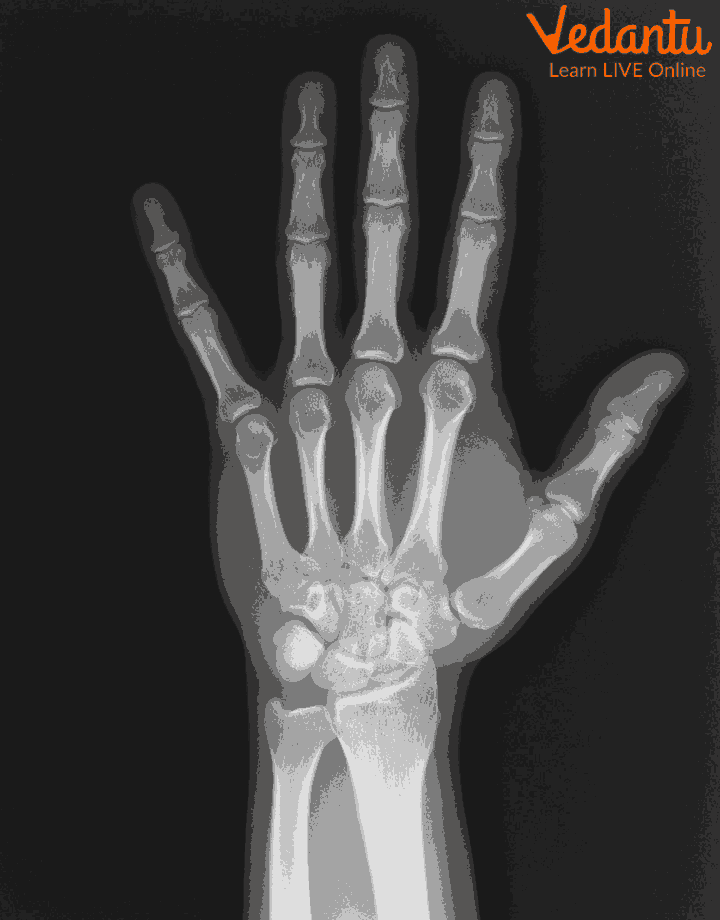

There are dense materials present inside our body for example bones, they can absorb the radiations of x-rays.

In the areas which are exposed to x-rays, they develop a film called x-rays film. White areas in the film show denser regions of the body for example bones which absorb x-rays and black areas on an x-ray show the soft tissues from which x-rays have not passed.

Medical uses of x rays include detection of any breakage in bones of humans.

Bone x-ray

Ans: The most common types of x-rays are chest x-rays, bone x-rays, hand x-rays, joint x-rays, dental x-rays and many more.